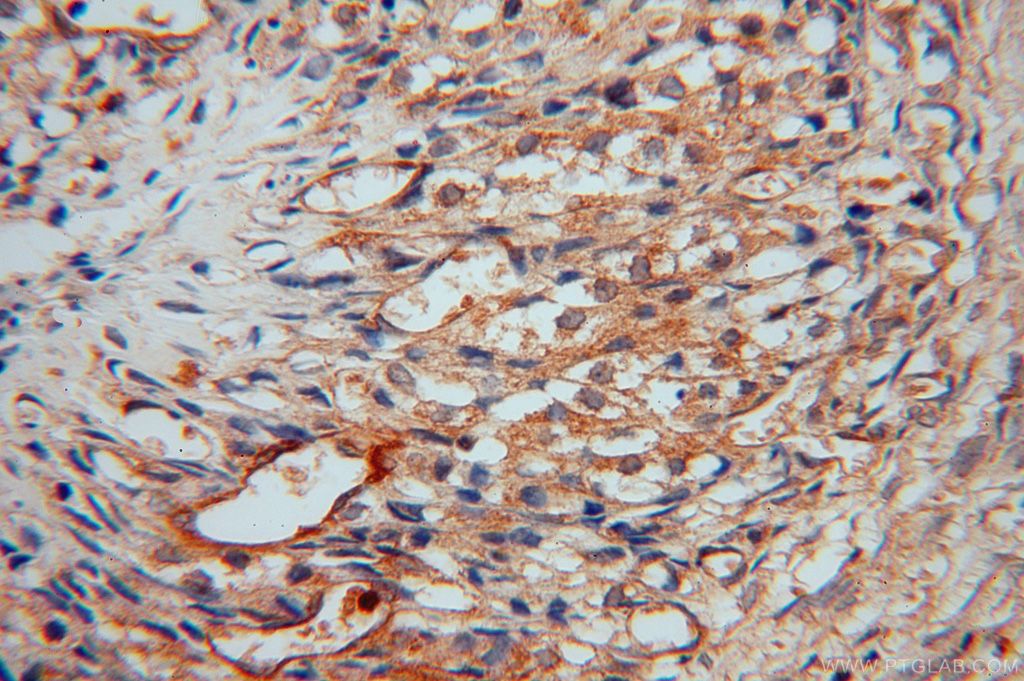

| Positive IHC detected in | human placenta tissue, human skin tissue, human ovary tissue, mouse kidney tissue, human colon Note: suggested antigen retrieval with TE buffer pH 9.0; (*) Alternatively, antigen retrieval may be performed with citrate buffer pH 6.0 |

| Immunohistochemistry (IHC) | IHC : 1:200-1:800 |